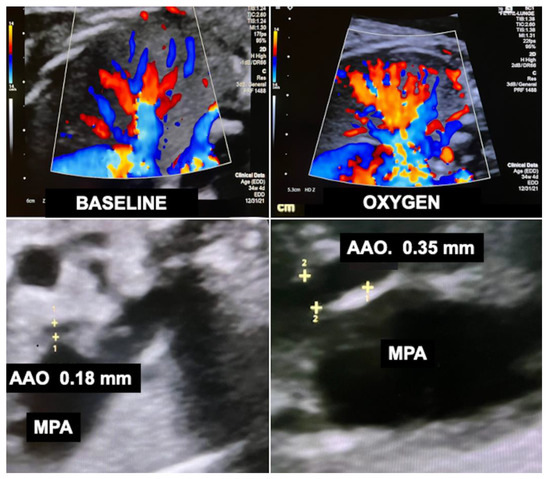

Recently, I observed that chronic intermittent materno–fetal hyperoxygenation can also effectively be used in fetuses with hypoplastic left heart syndrome and aortic atresia. Here, the approach promotes higher amounts of retrograde flow across the fetal aortic arch into the ascending aorta and from there into the coronary arteries to meet the needs of the increased cardiac workload. As a result of prenatal hyperoxygenation, extremely hypoplastic ascending aortas—a known risk factor for postnatal palliative surgery in neonates with hypoplastic left heart syndrome—as well as the aortic arch become larger, which may facilitate postnatal treatment (Figure 12). Another advantage of chronic hyperoxygenation in fetuses with hypoplastic left heart syndrome is that this subgroup benefits particularly well by achieving significantly larger head circumferences and increased intracranial volumes compared to those that did not undergo this therapy [110].

Figure 12.